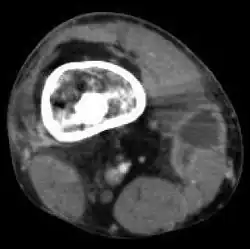

Le scanner

Il permet d'étudier surtout l'extension osseuse dans les formes chroniques (aspect hétérogène) et surtout de détecter la présence d'un séquestre, fragment d'os mort qui agit comme un corps étranger et favorise la persistance des fistules : c'est un élément essentiel de l'indication chirurgicale dans les suppurations persistantes. Il permet également d'étudier les localisations vertébrales et sacro-iliaques.